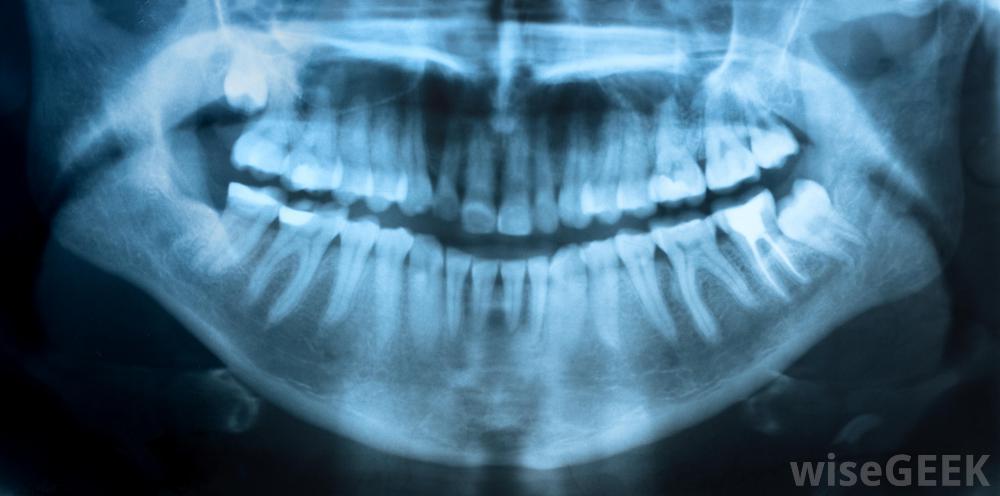

有时需要X光片来评估沟口造成的组织破坏程度通常存在于口腔中的细菌会失控生长,正是这种过量的有害细菌导致了牙龈的感染反过来,感染会损害牙龈组织。细菌填充的溃疡形成,通常含有少量食物和变质组织。没有人确切知道细菌是如何破坏牙龈组织的,但是这种损伤是很严重的。

一个简单的牙科检查就可以诊断出沟口通过简单的牙科检查进行诊断。在某些情况下,x光检查是必要的,以确定疾病造成的组织破坏程度,以及检测现有感染的程度。有时需要进行血液检查来确定感染是否已扩散到身体的其他部位。例如,这种感染可能导致一种潜在的致命疾病,称为坏死性口炎。这种情况在免疫系统受损的人群中最为常见。